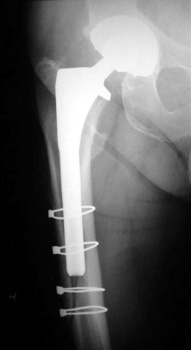

Intraoperative fracture of the femur at the tip of the femoral stem.

Femoral shaft fracture fixed with cerclage cables.